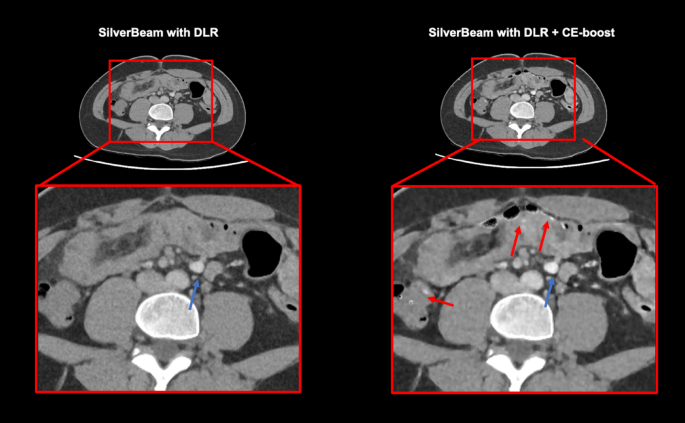

Table 4 shows the results of the subjective image analysis comparing different CT protocols: standard dose with IR, SilverBeam with DLR, and SilverBeam with DLR + CE-boost. Both observers rated SilverBeam with DLR as comparable to SilverBeam with DLR and standard-dose CT with IR in terms of overall image quality (p = 0.320 and p = 0.980), image noise (p = 0.570 and p = 0.990), artifacts (p = 0.070 and p = 0.999), and diagnostic acceptability (p = 0.999 and p = 0.970). Observer 2 found no significant difference in artifacts (p = 0.811) and diagnostic acceptability (p = 0.970) between SilverBeam with DLR + CE-boost and standard dose with IR. In contrast, observer 1 rated SilverBeam with DLR + CE-boost as inferior to standard-dose CT with IR regarding artifacts and diagnostic acceptability, primarily due to the presence of spotty high-density artifacts in the bowels (p < 0.001) (Fig. 4). The interobserver agreement reached a k value of 0.24, indicating fair agreement.

A comparison between reduced-dose computed tomography (CT) with deep DLR images, with and without CE-boost. Although, CE-boost markedly increased CT attenuation (blue arrow) even at reduced dose levels using SilverBeam filter, spotty high-density artifacts (red arrows) were observed in the bowel. These artifacts resulted from misregistration between non-contrast and CE images, exacerbated by motion artifacts. DLR deep learning reconstruction; CE contrast-enhanced.